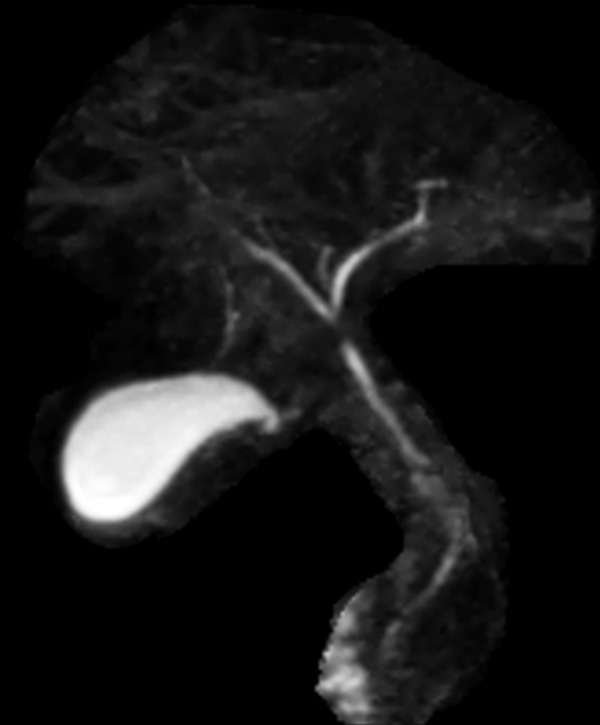

3D MRCP (MIP)